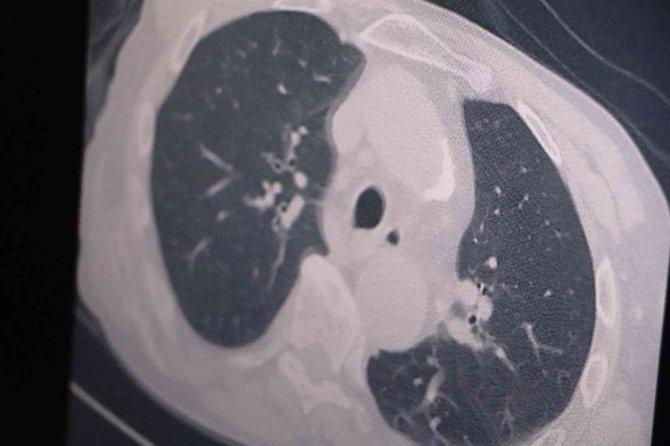

Son günlerde vakalarda ciddi bir artış gözlendiğini ve bu durumun halk arasında panik oluşturmaya başladığını aktaran Prof. Dr. Özkaya, "Özellikle geçen yılın bu zamanlarındaki vaka sayılarına göre neredeyse 3 katına aşkın vakalarımız var. Türkiye'de geçen yıl bu günlerde 5 bin civarında vaka varken 50'ye yakın ölüm vardı. Bir sene sonra yine aynı günlerde yaklaşık 3 katı yani 10-15 binlere varan günlük vaka sayısı var ama ölen ve yatan hasta sayısı neredeyse yok denecek kadar azdır. Yoğun bakımlarda yatan hastaların büyük bir çoğunluğu genel durumu düşkün olup da tesadüf pozitif gelen hastalardır. Yoksa aşılarını tam olan kişilerde hala akciğer tutulumu gözlenmiyor. Olduğunuz aşıların hala omicron varyantında akciğere inmesini önlediğini görüyoruz" dedi.

Aşının etkisinden kaçan yeni mutasyonlar olursa akciğer tutulumları ve yoğun bakım yatışlarının olacağını beklediklerini ifade eden Özkaya, "Şu an için mevcut aşıların hala etkili olduğunu görüyoruz. Çünkü yoğun bakımda ve servislerde yatan hastalarda ciddi akciğer tutulumunun olmadığını görüyoruz. Özellikle hacdan dönen vatandaşlarımız hacda karşılaştıkları orta doğu virüsleriyle ilgili etkileşim içinde oldukları için bu vatandaşlarımızda mutasyon olma ihtimali var. O yüzden hacdan gelenleri karşılarken mümkün olduğunca mesafe kurallarına dikkat edeceğiz" diye konuştu.